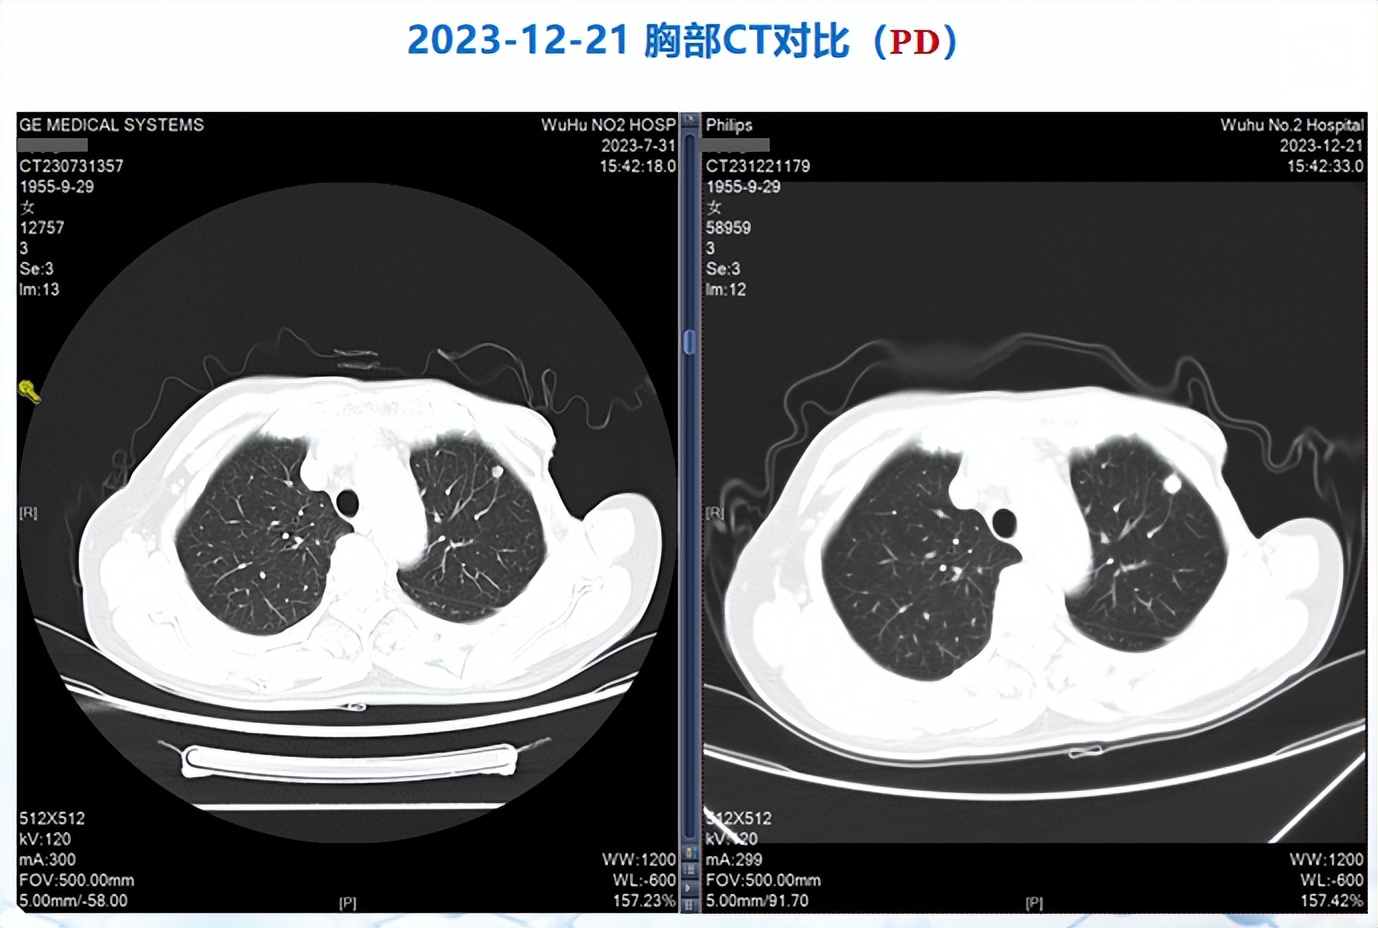

2023-12-20,患者复查胸部CT提示肺结节较前增大,考虑转移;查全腹部CT平扫+增强提示肝右前叶占位,考虑转移;同期(2023-11-22)患者辅助检查提示存在甲状腺减退,促甲状腺素>150 mIU/L。

△患者肺转移灶影像变化